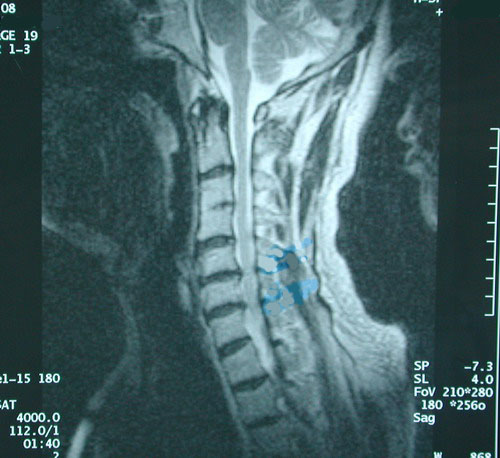

这种情况,需拍CT或MRI才能发现(见下图右)。拍X光片是发现不了的。

椎间盘变性、变扁,又引发了颈椎四周的韧带松弛、椎体滑脱、骨质增生、侧隐窝及椎间孔狭窄……。(见下图)